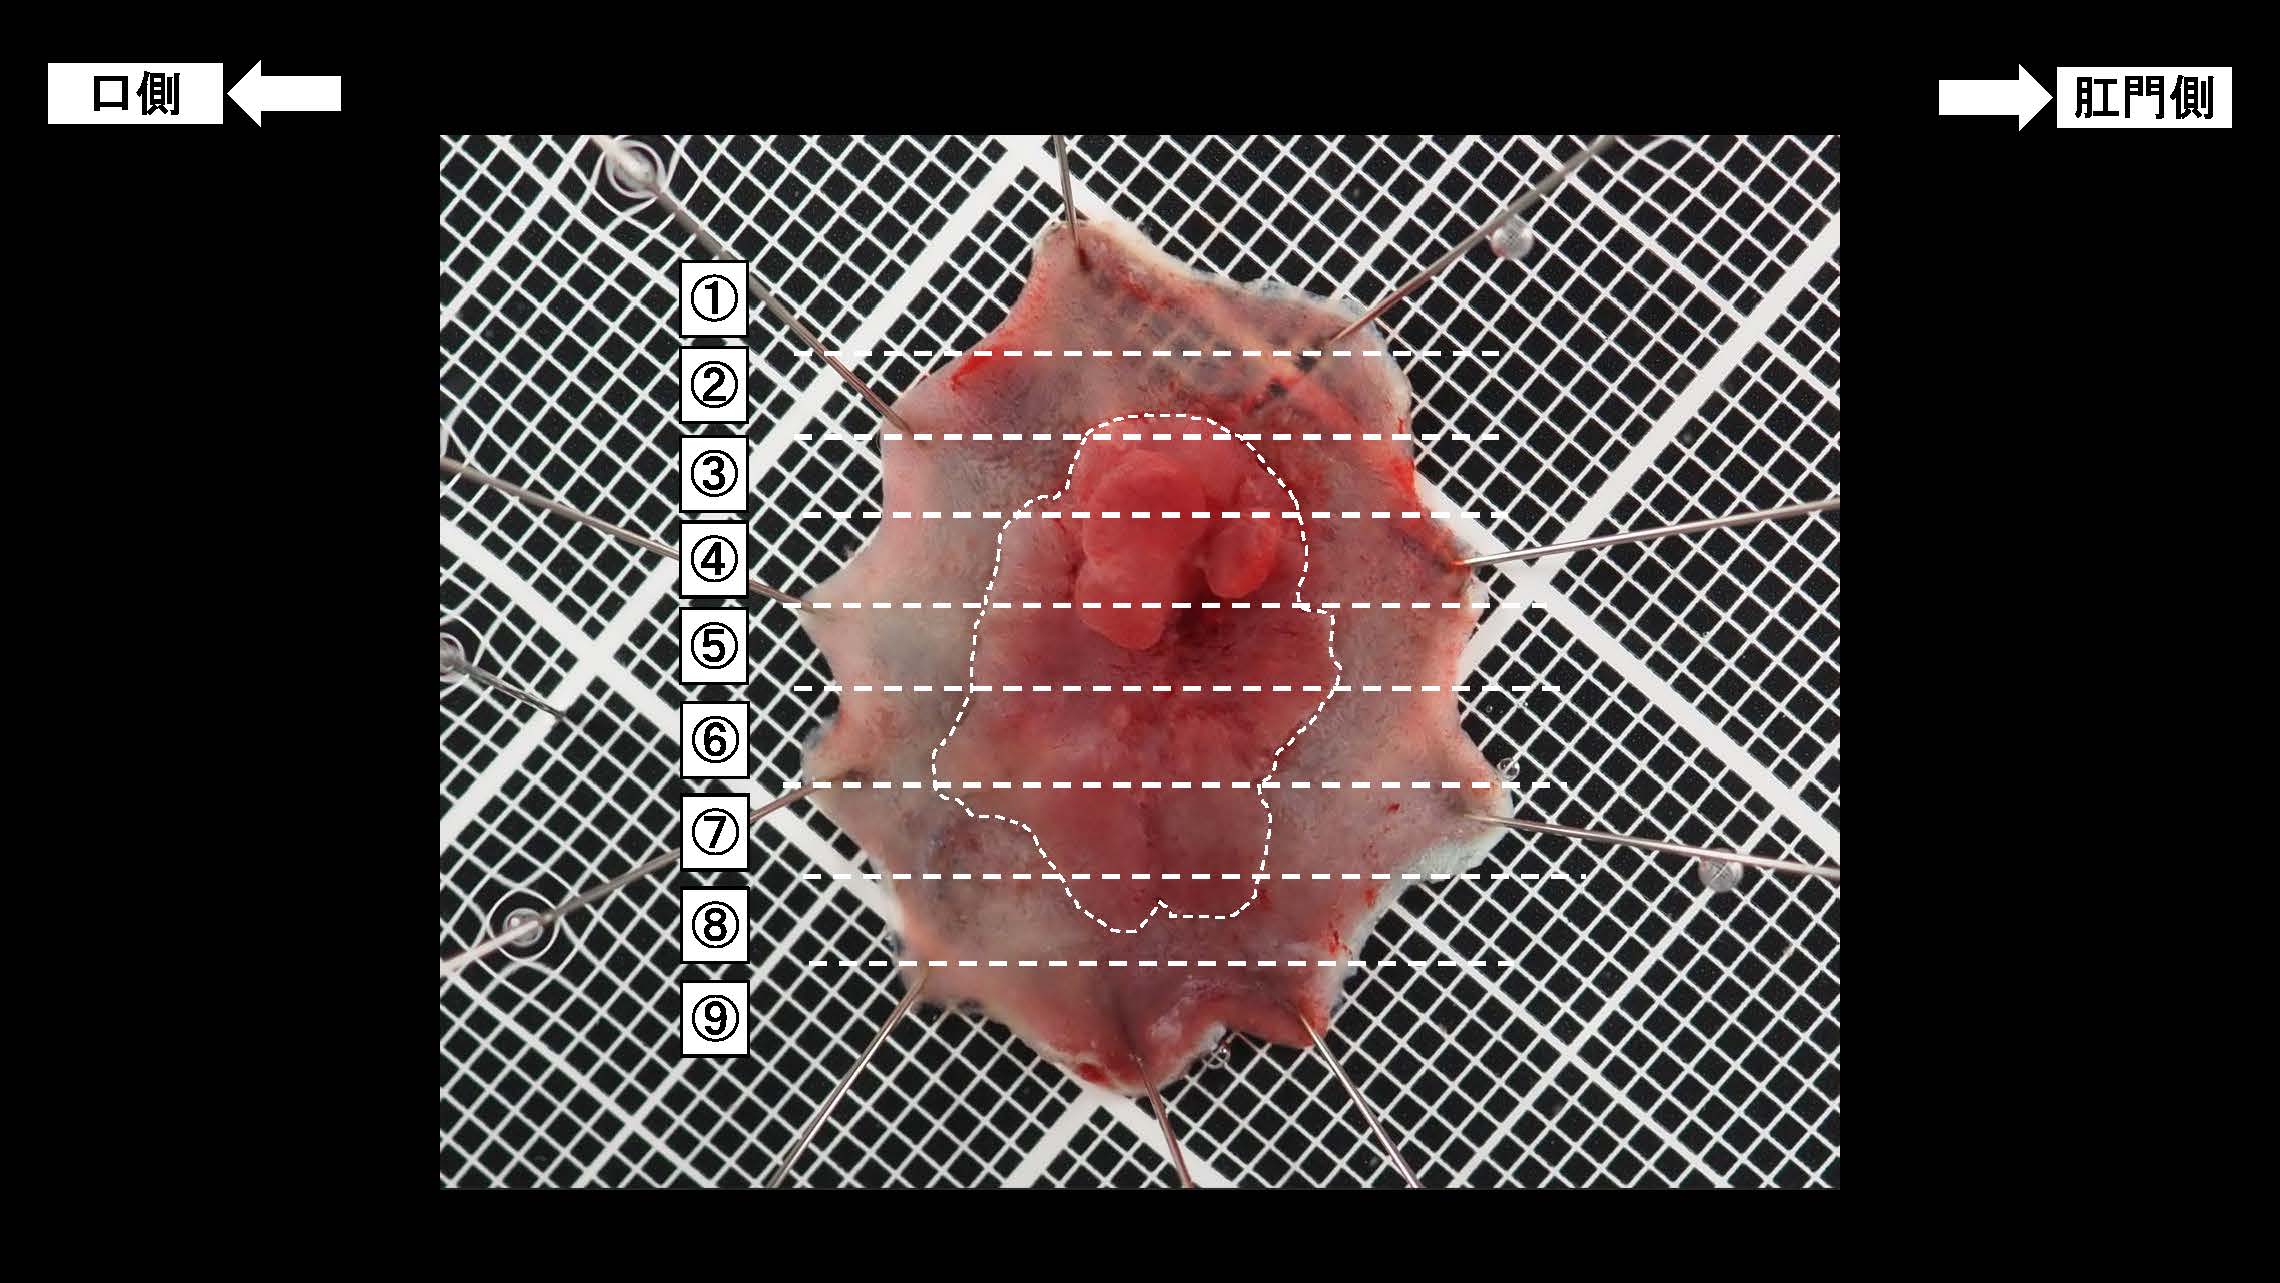

消化管Mapping~大腸~ 2025.6.11

内視鏡検査・治療

消化管Mapping